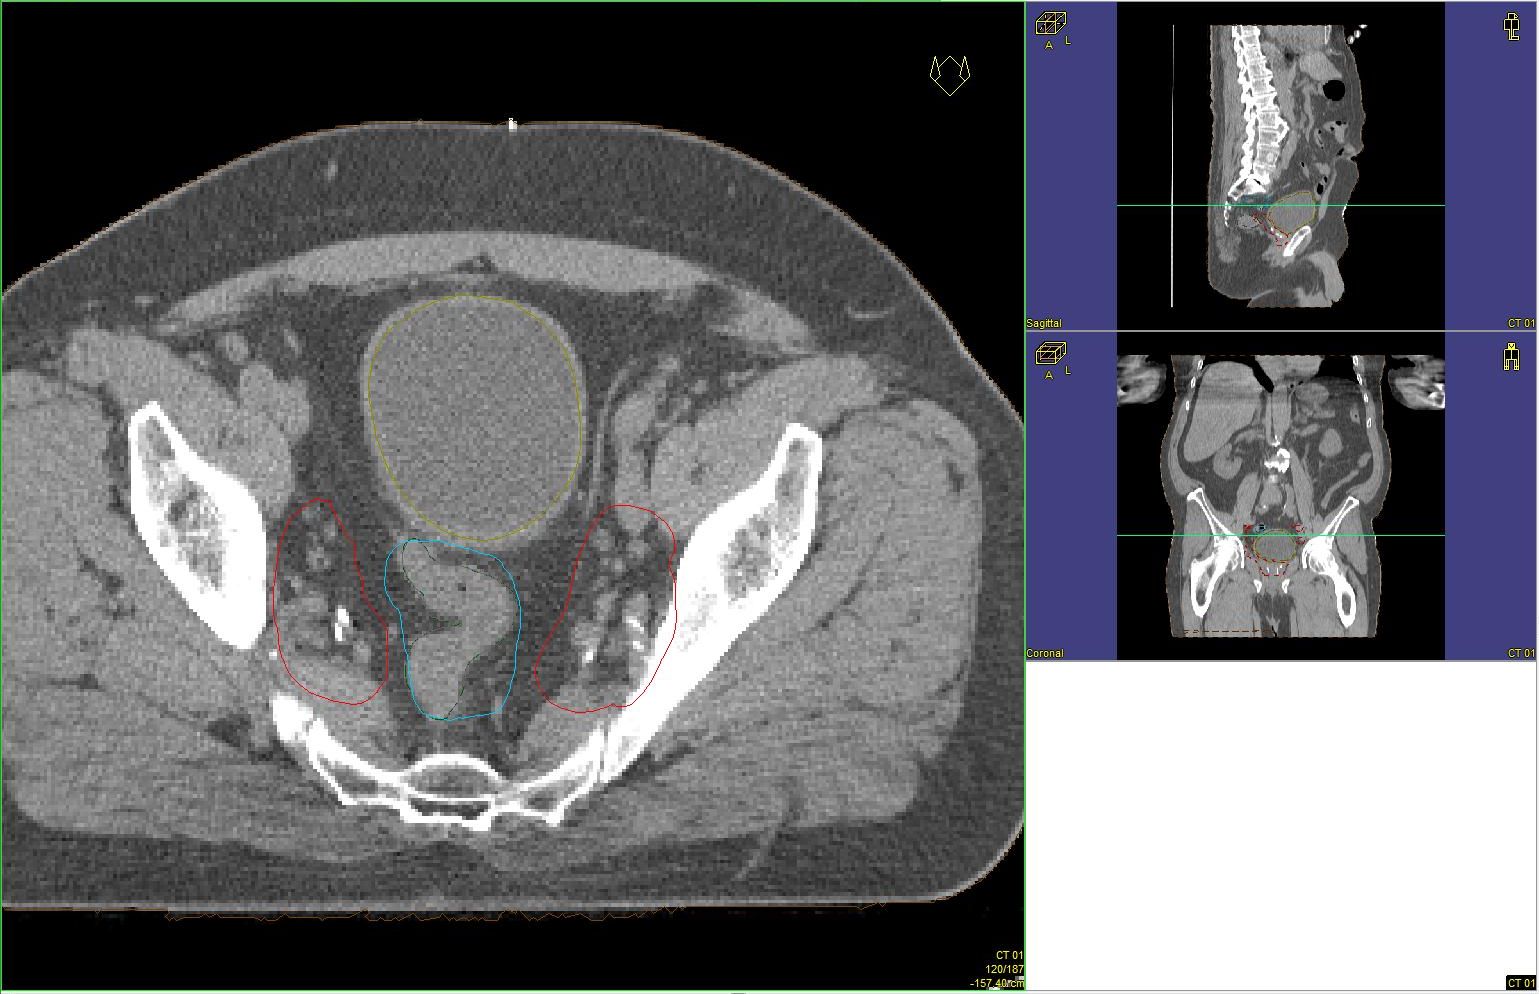

Prostata-Ca: Zielvolumen der postoperativen Radiotherapie

Beispiel: postoperative RT